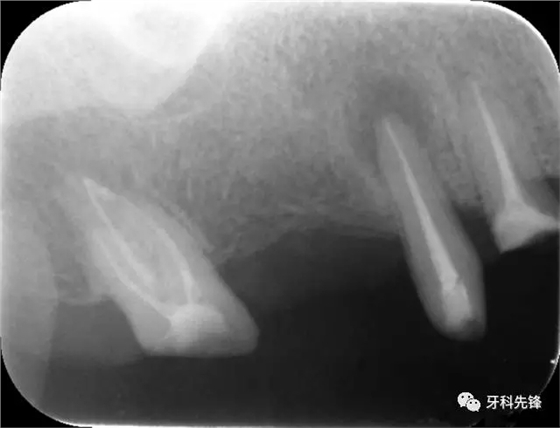

圖1術(shù)前X光片

640.webp.jpg

640.webp (1).jpg

640.webp (2).jpg